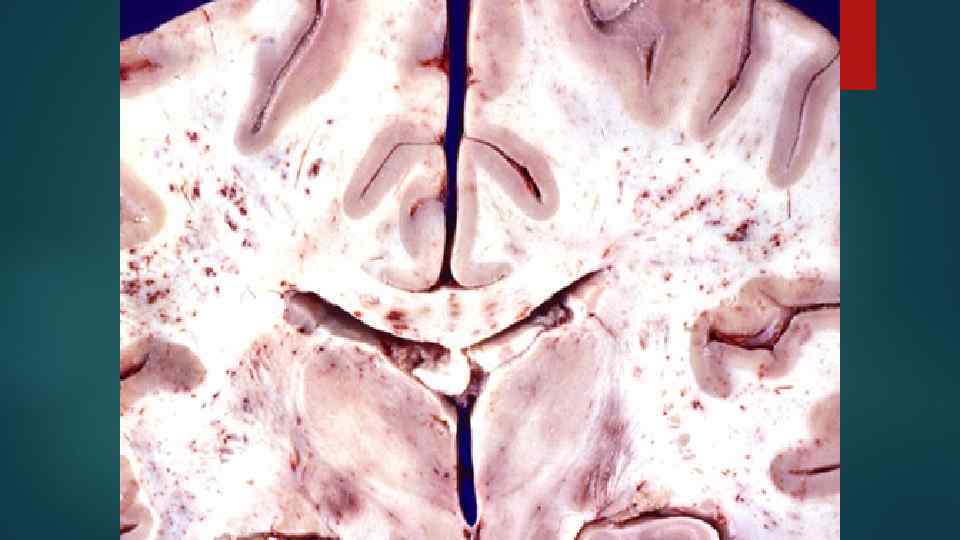

4. Инфильтрация КМ приводит к подавлению: лейкопоэза тромбоцитопоэза (Тr-пения) эритроцитопоэза (анемия). 5. В большинстве случаев лейкозные клетки поступают в кровь. 6. Лейкозные клетки могут инфильтрировать также печень, селезенку, л/у, любой другой орган и любую ткань.

Морфология лейкемии 1. Лейкемические инфильтраты в КМ, печени, селезенке, л/у и др. органах с их ↑.

Лейкемические инфильтраты (расположение) Орган ХМЛ ХЛЛ Селезенка пульпа фолликулы с увеличением резким их Печень по ходу капсулы, в синусоидах капсула, портальные тракты, образование лимфом Легкие по ходу альвеолярных перегородок перибронхиально Характерны • лейкемические тромбы в сосудах многих органов (инфаркты) • бластные кризисы • лейкемические тромбы не характерны • инфекционные осложнения, гемолитическая анемия (гемосидероз), Тр-пения